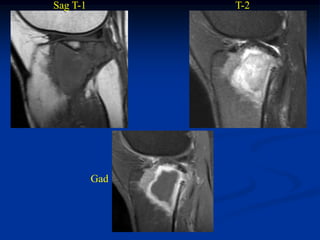

Case #1096

18 year male with

adamantinoma tibia

Bone scan

Sagittal T-2 MRI

Axial T-2 MRI